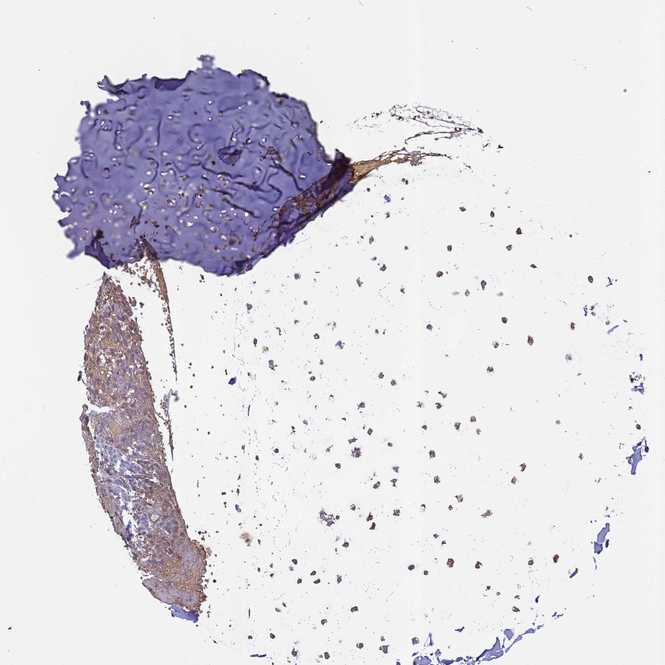

SOFT TISSUE 2 - Antibody stainingi

Antibody staining in the annotated cell types in the current human tissue is reported as not detected, low, medium, or high, based on conventional immunohistochemistry profiling in selected tissues. This score is based on the combination of the staining intensity and fraction of stained cells.

Each image is clickable and will lead to virtual microscopy that enables deeper exploration of all samples and also displays staining intensity scores, fraction scores and subcellular localization as well as patient and tissue information for each sample.

Antibody HPA017963

Chondrocytes Low

Fibroblasts Not detected